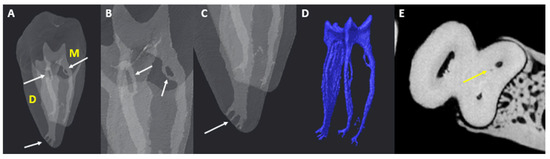

A Micro-Computed Tomographic Evaluation of Root Canal Morphology of Mandibular First Molars in a Black South African Subpopulation

Background: This study evaluates the root canal anatomy (main and accessory canals) of mandibular first molars in Black South Africans using micro-computed tomography. The effect of sex, arch side, and age are also investigated. Methods: The number of root canals in [...] Read more.

Background: This study evaluates the root canal anatomy (main and accessory canals) of mandibular first molars in Black South Africans using micro-computed tomography. The effect of sex, arch side, and age are also investigated. Methods: The number of root canals in each tooth and individual roots (including an observation of the middle-mesial and middle-distal canals), the number of accessory canals, accessory canal type, root canal thirds, and the prevalence of apical deltas were recorded. A chi-squared test of association (p < 0.05) was used to report on variables (sex, arch sides, and age). Results: In most teeth, either three (55.81%) or four canalled (24.42%) configurations were present. The middle-mesial canal was found in 18.6% of teeth (males and females), with a higher prevalence among females (23.68%). The middle-distal canal was found in 3.49% of teeth. Chamber canals were identified in 4.7% of teeth. Accessory canals most likely located in the apical third were found in approximately 84.9% and 86.1% of mesial roots and distal roots, respectively. Apical deltas were identified in 15.12% of mesial and 20.93% of distal roots. Conclusion: Root canal anatomy in this population is diverse and includes differences in arch sides between the sexes. Full article